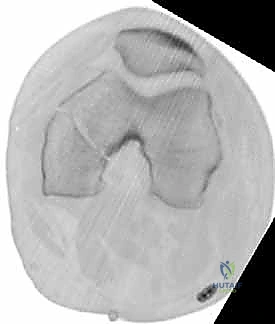

- الأشعة السينية (X-Rays): أخذ صور من زوايا متعددة (أمامي خلفي، وجانبي) لتحديد موقع الكسر ونوعه.

- الأشعة المقطعية (CT Scan): وهي ضرورية جداً في كسور عظم الفخذ البعيدة، خاصة إذا كان الكسر يمتد إلى داخل مفصل الركبة (Intra-articular fractures). تساعد الأشعة المقطعية الدكتور هطيف على بناء نموذج ثلاثي الأبعاد للكسر، مما يسهل التخطيط الجراحي وتحديد أماكن وضع المسامير بدقة.